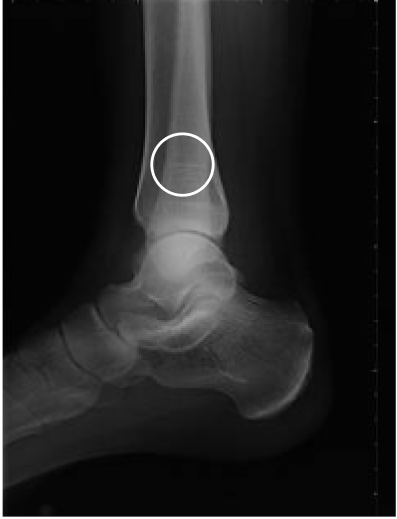

Tibial fracture

age 57

Femur fracture

age 13

Metatarsal fracture

age 16